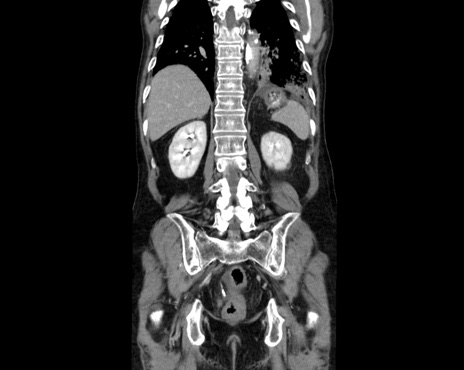

症例26(冠状断像)

【症例】80歳代男性

【主訴】嘔吐

【現病歴】昨晩2回嘔吐あり、今朝になっても嘔吐あり。来院。

【既往歴】胃潰瘍

【身体所見】意識清明、BT 37.6℃、BP 166/95mmHg、HR 100bpm、SpO2 97%、腹部:平坦・軟、腸蠕動音聴取良好、圧痛なし。

【データ】WBC 21900、CRP 1.4